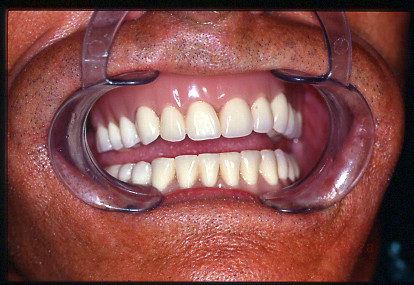

REHABILITACIÓN DE AMBOS MAXILARES CON MESOEXTRUCTURA SOBRE IMPLANTES.

CASO CLÍNICO REHABILITACIÓN CON MESOEXTRUCTURA FIJA EN MAXILAR SUPERIOR Y REHABILITACIÓN CERÁMICA EN MAXILAR INFERIOR EN PACIENTE CON PERIODONTITIS AVANZADA DEL ADULTO

MESOEXTRUCTURA EN PACIENTE CON ENFERMEDAD PERIODONTAL.